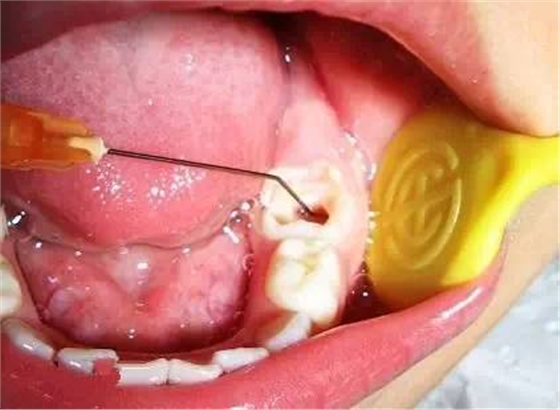

用有效溫和的根管沖洗液體,生理鹽水,稀釋了的雙氧水,0.5%的次氯酸鈉。來清除根管內(nèi)的腐敗組織和碎屑,將小號的根管擴(kuò)大器械插入根管內(nèi)。不超過藍(lán)色30#的,常用25#紅色以下的。插入長度比X光線片子的根尖位置短2-3毫米。輕柔地銼洗或蕩洗根管壁,再次沖洗去除碎屑污物。因為乳牙的根管壁非常薄,所以不要刻意去根管成形,銼除牙本質(zhì)。這是和成人的不同。

B,建議在每次換藥前,用棉捻或是買點紙尖擦干根管,不要插入過深。

2)根管預(yù)備

根管沖洗

3)封藥

4)根充,乳牙根充須用能吸收的糊劑。然后進(jìn)行常規(guī)充填或冠修復(fù)

(以上圖片引用自福建醫(yī)大附屬口腔醫(yī)院兒童科 高生輝老師的課件,非常感謝!)

去齲,開髓,揭髓室頂。根管預(yù)備,根管沖洗。封藥。根管充填。